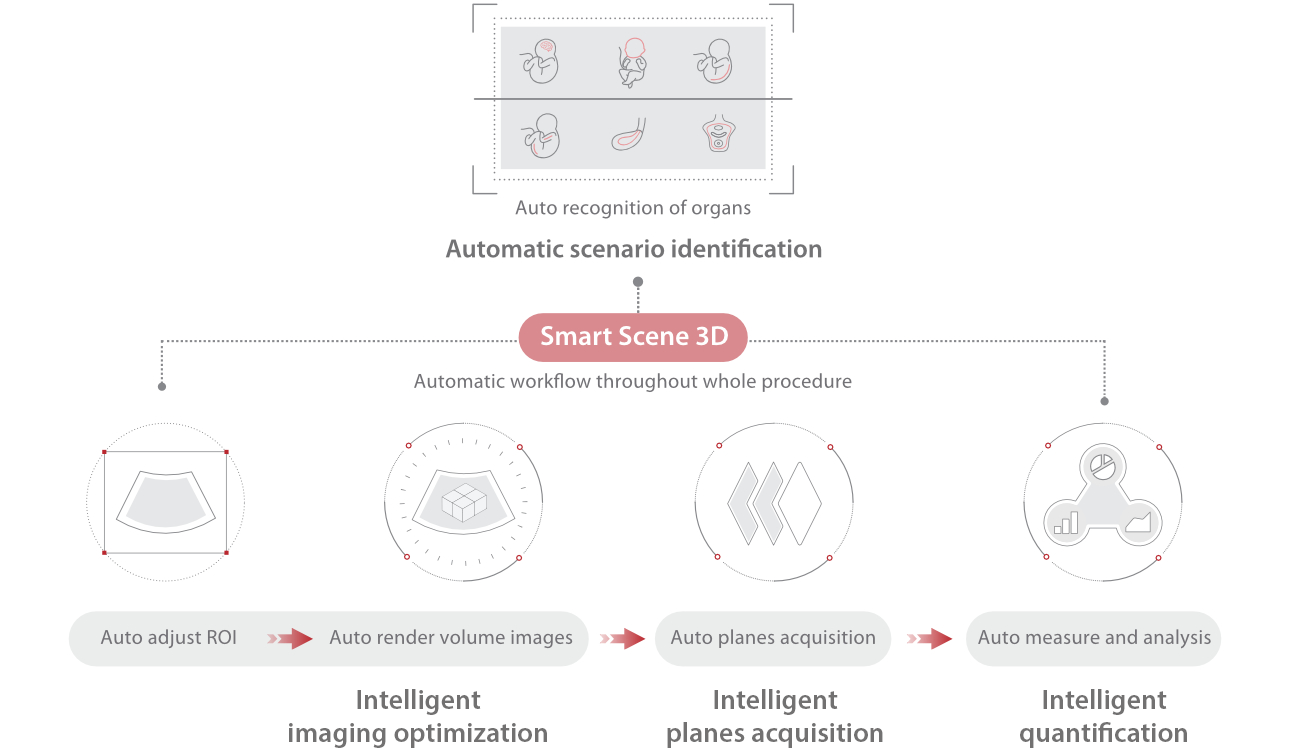

Intelligenza completa orientata allo scenario clinico

L'innovativa soluzione Smart Scene 3D consente l'identificazione automatica delle caratteristiche dei tessuti e fornisce una diagnosi specifica per i diversi distretti di esame durante l'intera procedura. Questa innovazione aumenta lŌĆÖaccuratezza e la sicurezza diagnostica, migliorando lŌĆÖefficienza.